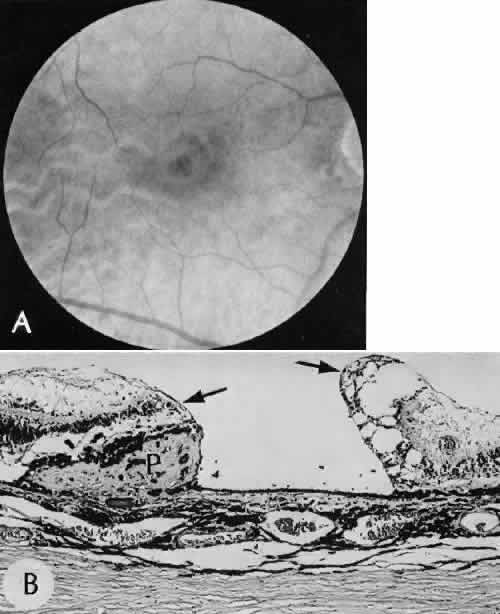

Fig. 31. A case of choroidal detachment. A. By fundus reflex, a large dome-shaped mass can be seen originating from the choroid. The differential diagnosis would include uveal malignant melanoma. In this case, the clinical findings were due to choroidal detachment from the sclera because of fluid accumulating in the suprachoroidal space following cataract surgery. B. The histologic section from another case of choroidal detachment illustrates the location (arrow) and extent of the detachment. In this case the detachment extends to the region of the ciliary body limited anteriorly by the attachment of the choroid to the scleral spur. The displacement of the ciliary body will result in apparent shallowing of the anterior chamber. (Hematoxylin-eosin stain; × 6.)

Iris or lens capsular incarceration into the wound and extending to the conjunctival space (Figs. 32 and 33) may act as a wick through which aqueous can escape, causing a flat anterior chamber. Histologically, iris, which is frequently recognized only by the presence of melanocytes, is seen in the limbal scar, in the limbal episclera, or in both areas.